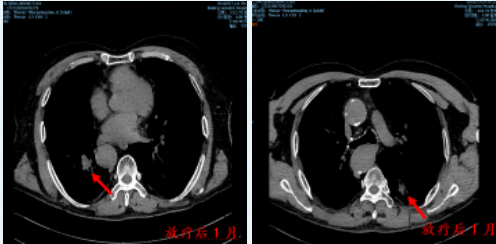

放疗后1月 胸部CT显示双侧病灶明显缩小

同年5月返院复查,胸部提示双肺转移灶较前明显缩小,未再行全身化疗,后按时复查双肺病灶持续缩小。

放疗后58个月 胸部CT显示双侧病灶控制良好

直至2023年3月返院复查病灶仍控制良好(放疗后4年零11个月),日常生活和活动不受影响,生活质量较高。